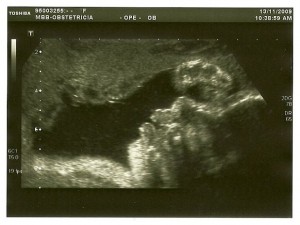

A fotografia em que ela ficou melhor é a seguinte, em que ela está com a mão direita perto do rosto! Por cima vê-se a placenta onde ela costuma encostar a face! Continua de cabeça para baixo, em posição cefálica.